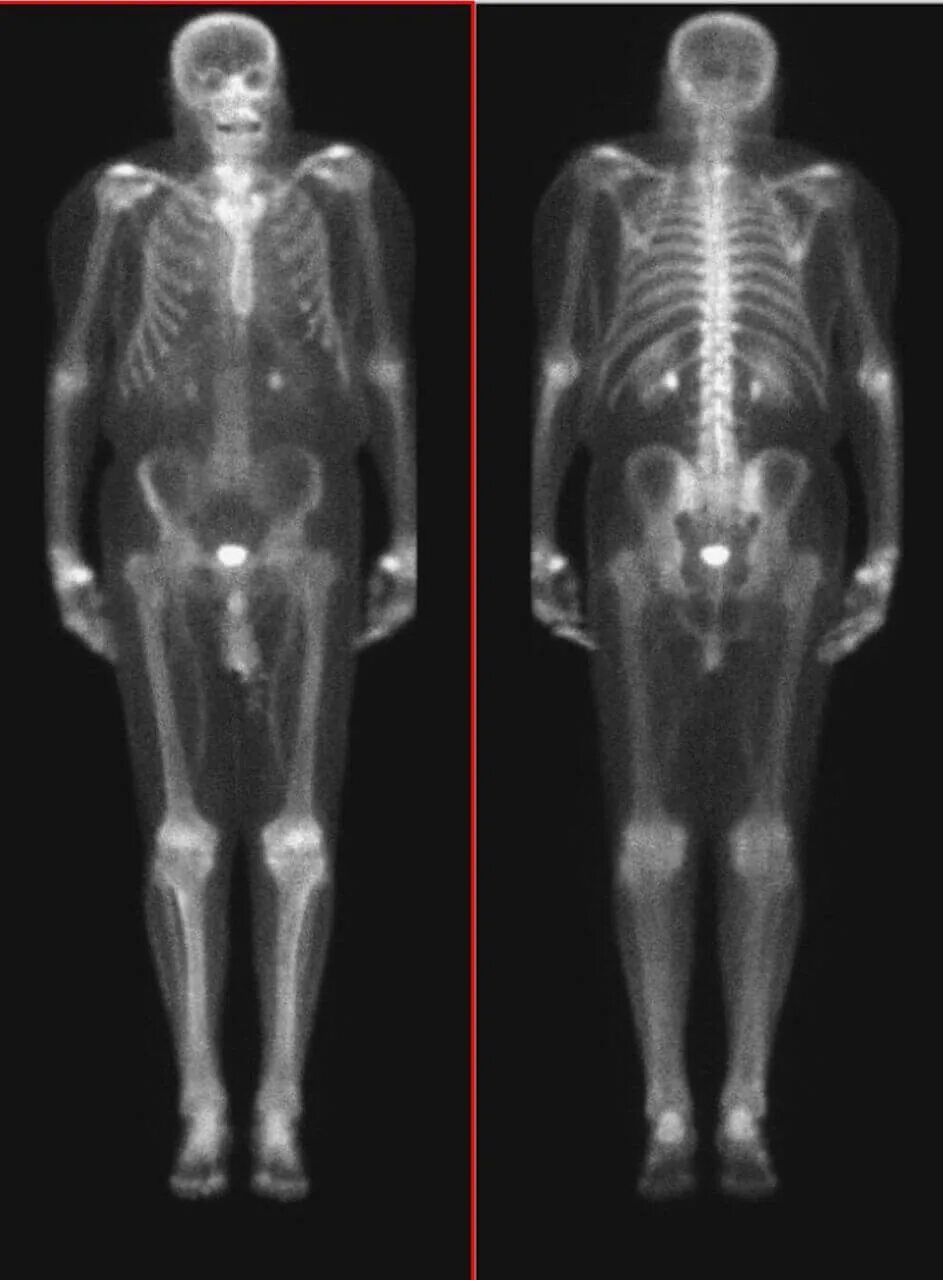

Как называется исследование костей